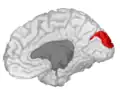

![]() Medial surface of left cerebral hemisphere. (Cuneus visible at left in red.) | |

The cuneus (from Latin 'wedge'; pl.: cunei) is a smaller lobe in the occipital lobe of the brain. The cuneus is bounded anteriorly by the parieto-occipital sulcus and inferiorly by the calcarine sulcus.